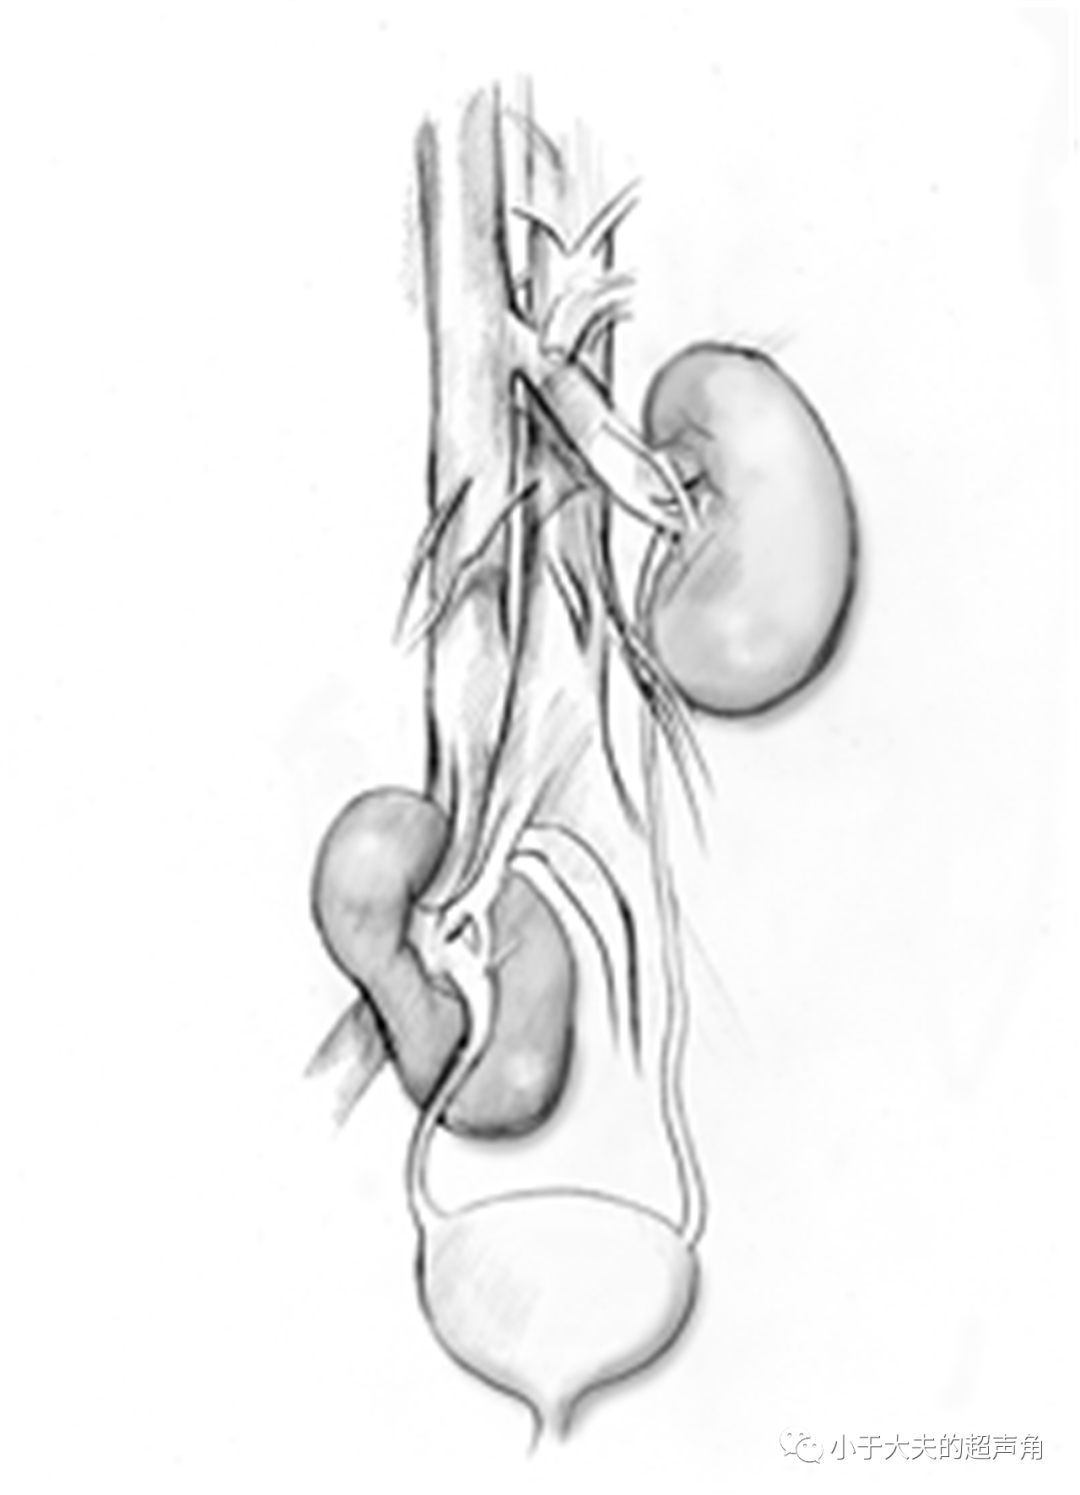

胎儿时期形成肾脏的肾胚芽位于盆腔之中 , 随着胎儿的生长 , 肾脏逐渐上升 。

此时如果供给肾脏的血管有位置上的变异 , 肾脏将随之有位置上的异常 。

如血管位置低 , 肾脏上升受限 , 甚至不能升出盆腔即盆腔肾 。 如血管位置过高或过长 , 肾脏位置也高或异位于对侧 。

常见异位肾类型有:盆腔肾、胸腔肾、交叉异位肾 。